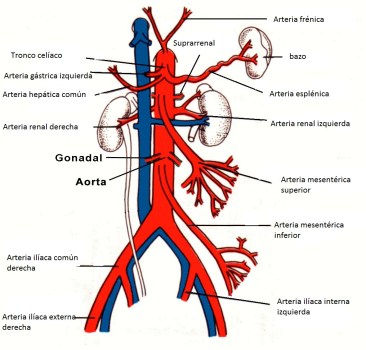

El intestino delgado y grueso está vascularizado por tres arterias que irrigan diferentes regiones:

1º- Tronco celiaco: vasculariza desde el esófago distal hasta la 2ª porción duodenal o duodeno descendente. Se compone de:

- Arteria gástrica izquierda.

- Arteria hepática común (se divide luego en gastroduodenal y hepática propia).

- Arteria esplénica.

2º- Arteria mesentérica superior (AMS): desde 3ª porcion duodenal hasta el colon transverso y flexura esplénica. Mencionar que la arteria gastroduodenal (primera rama de la hepática común) forma una importante conexión con la AMS.

La AMS forma otras importantes anastomosis con la AMI: arteria marginal de Drummond y la arcada de Riolano.

3º- Arteria mesentérica inferior (AMI): desde la flexura esplénica del colon hasta el recto. Forma además conexiones con las ramas lumbares, las arterias sacras e iliacas internas.

Las venas mesentéricas superior (VMS) e inferior (VMI) discurren paralelas a sus arterias y drenan la sangren de los diferrentes territorios subsidarios. La VMI se vacía en la vena esplénica, la cual se une a la VMS para formar la vena porta. En su discurrir, las venas mesentéricas forman anastomosis y colaterales con otras venas desde las gástricas y esofágica hasta renales, lumbares y pélvicas.